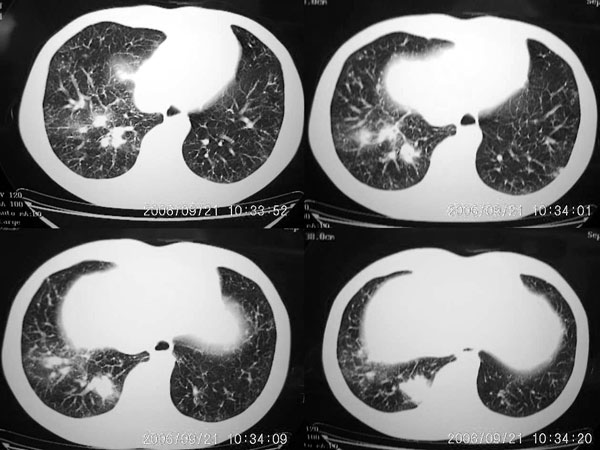

男 27岁 咳嗽一个月,治疗无效。

右肺下叶后段及右肺门附近见斑片状模糊影,密度不均,部分实变,右肺门附近见肿大淋巴结影.

两肺弥漫均匀分部粟粒壮影 右肺基底段不规则软组织密度影其内密度不均 纵隔内淋巴结钟大 请进一步右肺病灶薄层检查及补充病史后再会诊

右肺下叶后基底段结节样病灶,边界不规则,密度不均,右肺门团片影,肺门增大,纵隔见肿大淋巴结.结合临床首先考虑:肺结核.

图像显示:右下肺门增大,伴右下肺斑片状高密度影,密度不均;右下肺支气管管壁增厚,纵隔内淋巴结肿大。意见:支气管内膜结核、结节病。建议行纤支镜检查。

右下肺脊柱旁结节样肿块,可见毛刺,右侧肺门影增大,并见气管隆突前、主动脉窗内多发结节影。

右肺门影增大,纵隔内可见多个淋巴结肿大,右肺下叶内后基底段斑片状模糊影,两肺间质性改变;考虑右肺内结核并右肺门及纵隔淋巴结结核可能性大;职业病及结节病待排;肿瘤不太支持,年龄轻,无咯血,未见明显支气管狭窄,建议穿刺活检。

右肺门阴影增大,见有钙化,右肺下叶后基底段片状影,结合治疗史考虑右肺下叶结核

右下肺后基底段病灶虽然具有周围型肺癌的一些征象,但是它太虚了,纵肺比例过小,不到50%。而且在纵隔窗也显示该病灶比较虚,“块儿”比较小,内部也不实在,有小泡。

单就此病灶来说,考虑结核更为妥当。但问题是右肺门以及纵隔多组淋巴结肿大不太好解释,再有就是双肺的粟粒病灶,如果是血播的话应该有很明显的症状、体征的,不至于象楼主这般轻描淡写。

补充一点,患者体检近期有双侧颈部淋巴结肿大

右肺下叶后基底段结节样病灶,边界不规则,密度不均,右肺门团片影,肺门增大,纵隔见肿大淋巴结.

考虑1、纵隔及肺部淋巴瘤.2、结节病